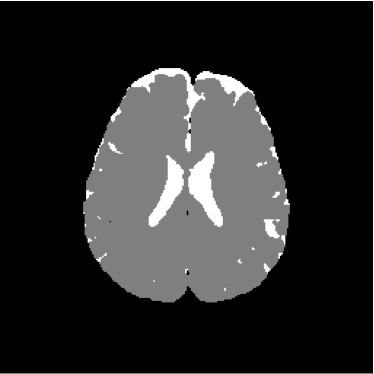

Figure 28 shows 13th slice of classification result obtained by the use of the objective dialectical classifier. Figure 29 exhibits 13th slice of classification result after performing post-labeling, whilst figure 30 shows the entire volume generated by ODC classification.

The training process of ODC algorithm resulted in 6 classes. These classes were reduced to 4 after manual post-labeling, merging 3 classes out of brain region, namely image background, noise and cranial box. The post-labeling is manual because all 3 cited regions are statistically different and, consequently, they are merged due to our interest in classes more related to the brain regions. On figure 29 it is possible to notice that ODC was able to distinguish white matter from the gray matter present in the interface between liquor and white matter.

Figure 29: 13th slice of objective dialectical classification after post-labeling